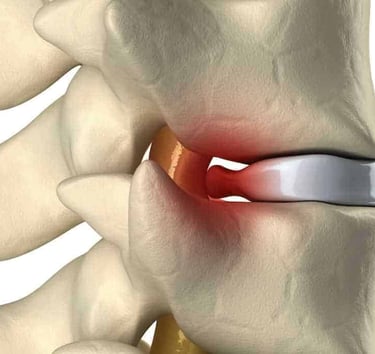

Cirugía de columna

Tratamientos avanzados para hernias de disco, ciática, estenosis espinal y otras patologías vertebrales.